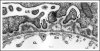

Figure 3

Electron micrograph of developing glomerular capillary loop. The endothelial cell (En) is large and contains only a few fenestrations at this stage. Only a few, relatively broad foot processes (fp) are present in the podocyte (Po) cell layer. A double basement membrane between the endothelium and podocytes can be seen clearly (arrows). Note the loose mesangial matrix (arrowheads) in the mesangium (M). Reproduced with permission (ref. 36).